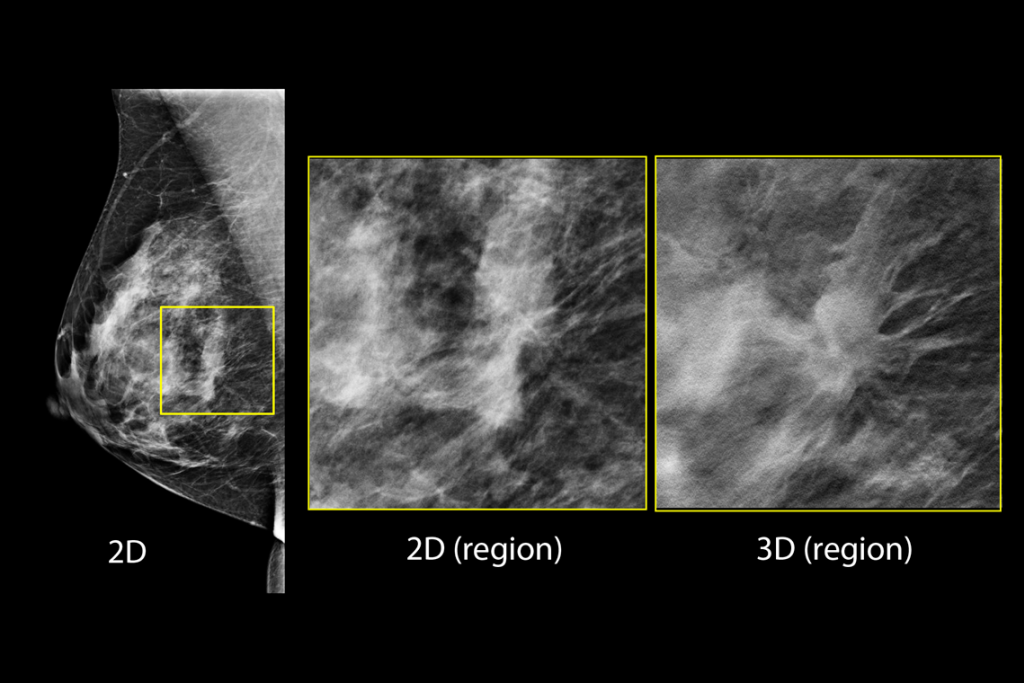

Tomosynthesis results that are proven to help you detect up to 65% more invasive breast cancers than 2D alone.3,**

The 3Dimensions mammography system works with smart tomosynthesis technology, combining Clarity HD™ high resolution imaging, Intelligent 2D™ synthesised imaging and 3DQuorum™ SmartSlices for an efficient workflow.